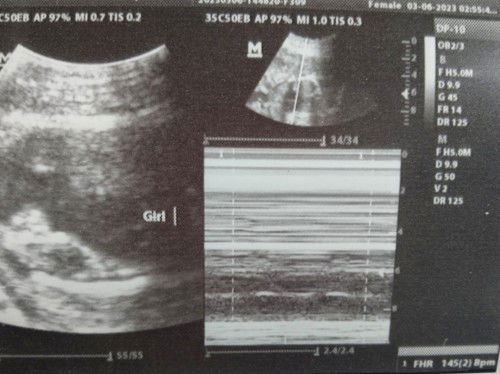

Mga mii, sana hindi na mabago etong gender na nakita ni OB sabi niya girl daw 80% isang ultrasound pa daw para sure, super excited ako kase guato ko talaga girl š„° sana merong marunong tumingin dito base sa ultrasound ko, girl ba talaga mga miii? āŗļø 28weeks and 2 days #TeamJuneš